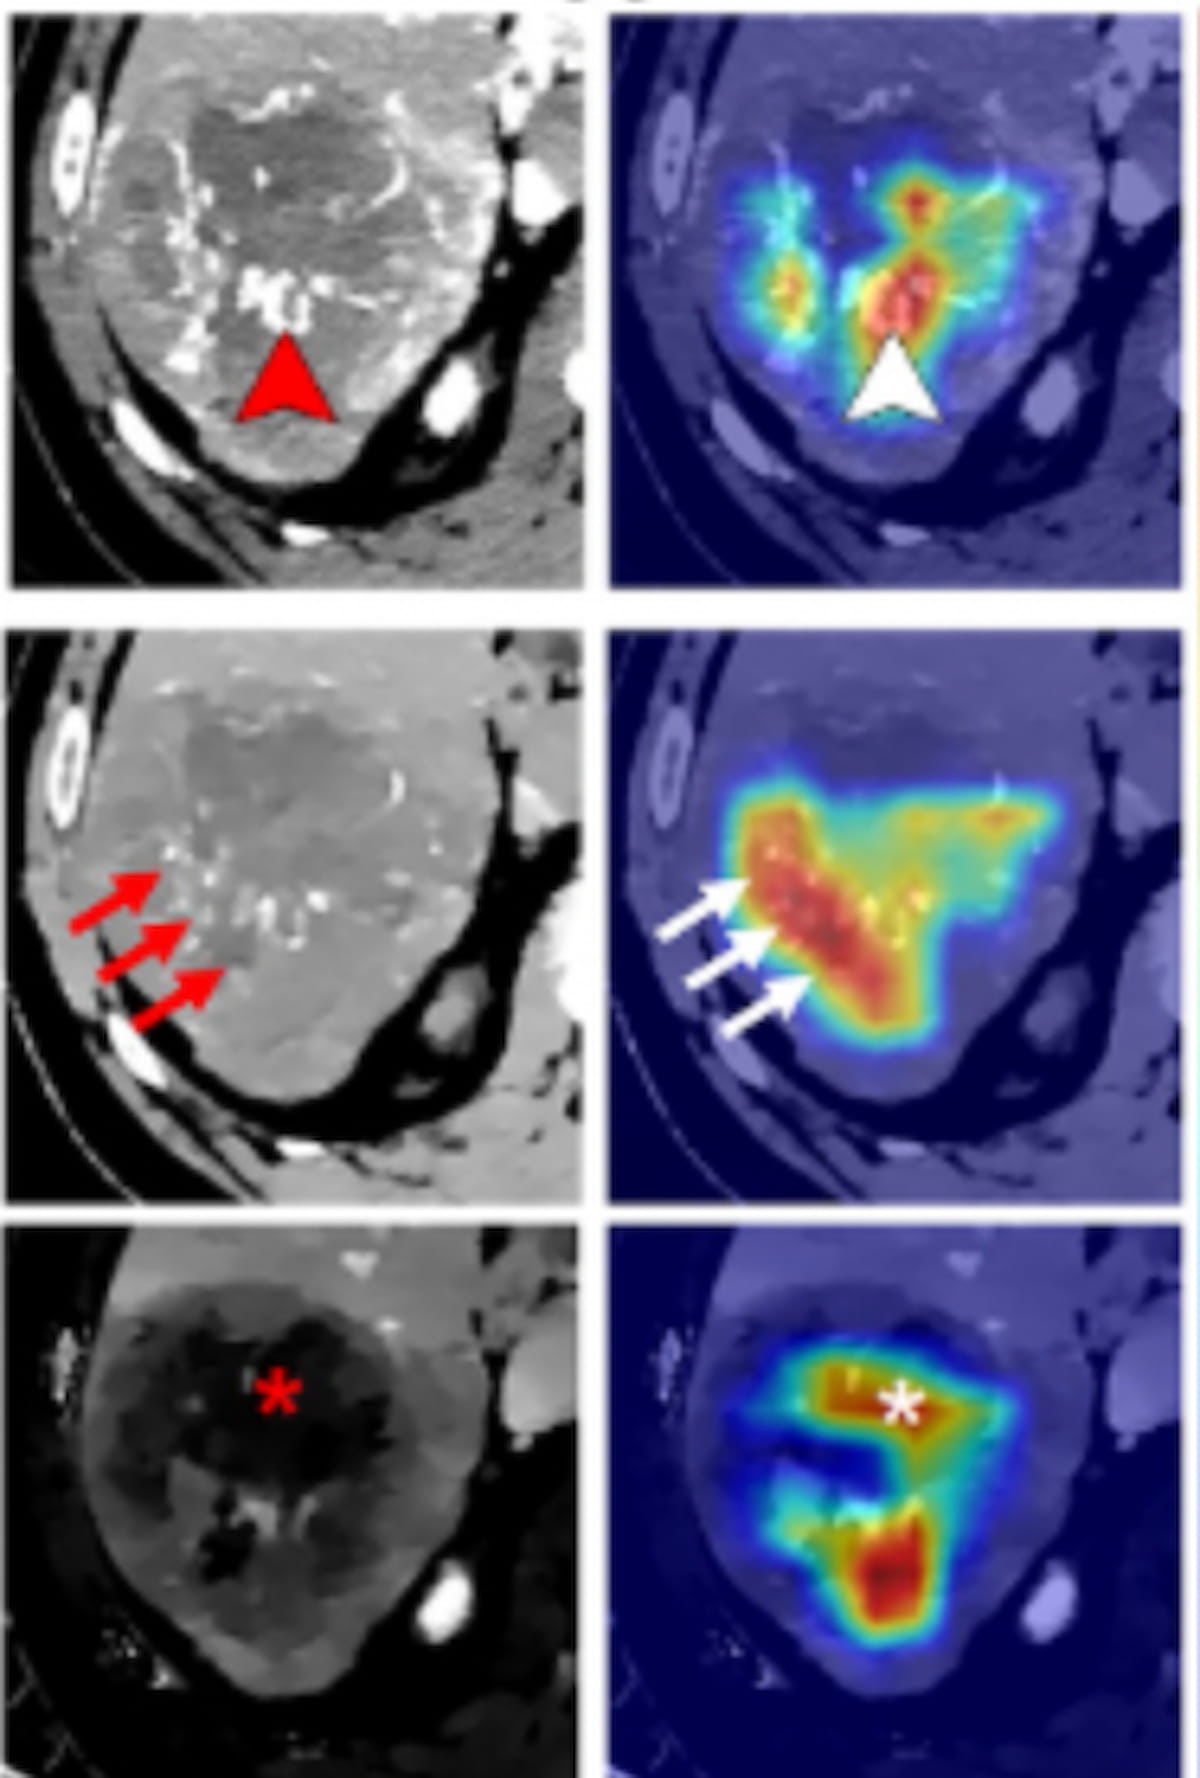

Yukarıdaki görüntüleme, hepatoselüler karsinomun (MTM) masif alt tipini geliştiren 65 yaşındaki bir erkeğe aittir. Görüntüleme, sanal arteriyel faz tek enerjili görüntüleri (VMI’ler), elektron yoğunluk haritalarını, portal venöz fazdaki iyot yoğunluk haritalarını ve karşılık gelen ısı haritalarını içerir. Resimler nezaketen ışınlar.

“Bu çok merkezli çalışmada, 100 ng/mL’den yüksek bir ⍺-fetoprotein seviyesi ve arteriyel fazın (AP), AP elektron yoğunluğunun ve iyot yoğunluğunun tek enerjili varsayımsal görüntülerinin derin öğrenme (DL) radyasyon modellerinin bulunduğunu bulduk. portal venöz faz, MTM belirlemesinden bağımsız belirleyicilerdi. Bu dört belirleyici, klinik radyometrik modelle karşılaştırıldığında eğitimimizde, dahili testlerimizde ve harici test veri kümelerimizde MTM HCC’yi tahmin etmede daha iyi performans gösteren DL radyomik grafik modeline dahil edildi…” , Çin’in Guangdong kentindeki Sun Yat-Sen Üniversitesi Üçüncü Bağlı Hastanesi Radyologlar Bölümüne bağlı MD Jin Wang ve meslektaşlarına dikkat çekti.